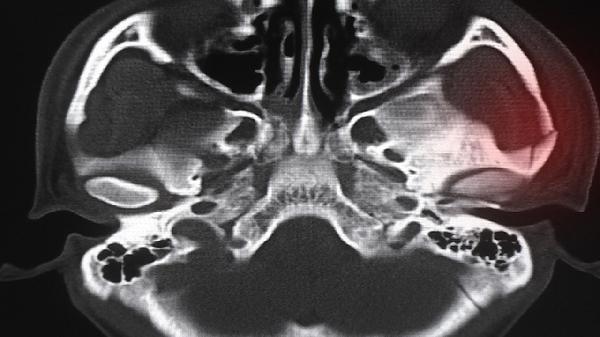

角膜炎(干燥型,创伤型,病原型)、角膜溃疡、角膜损伤或其他化学因素所致的角膜灼伤等。

| 【功能主治】 | 角膜炎(干燥型,创伤型,病原型)、角膜溃疡、角膜损伤或其他化学因素所致的角膜灼伤等。 |